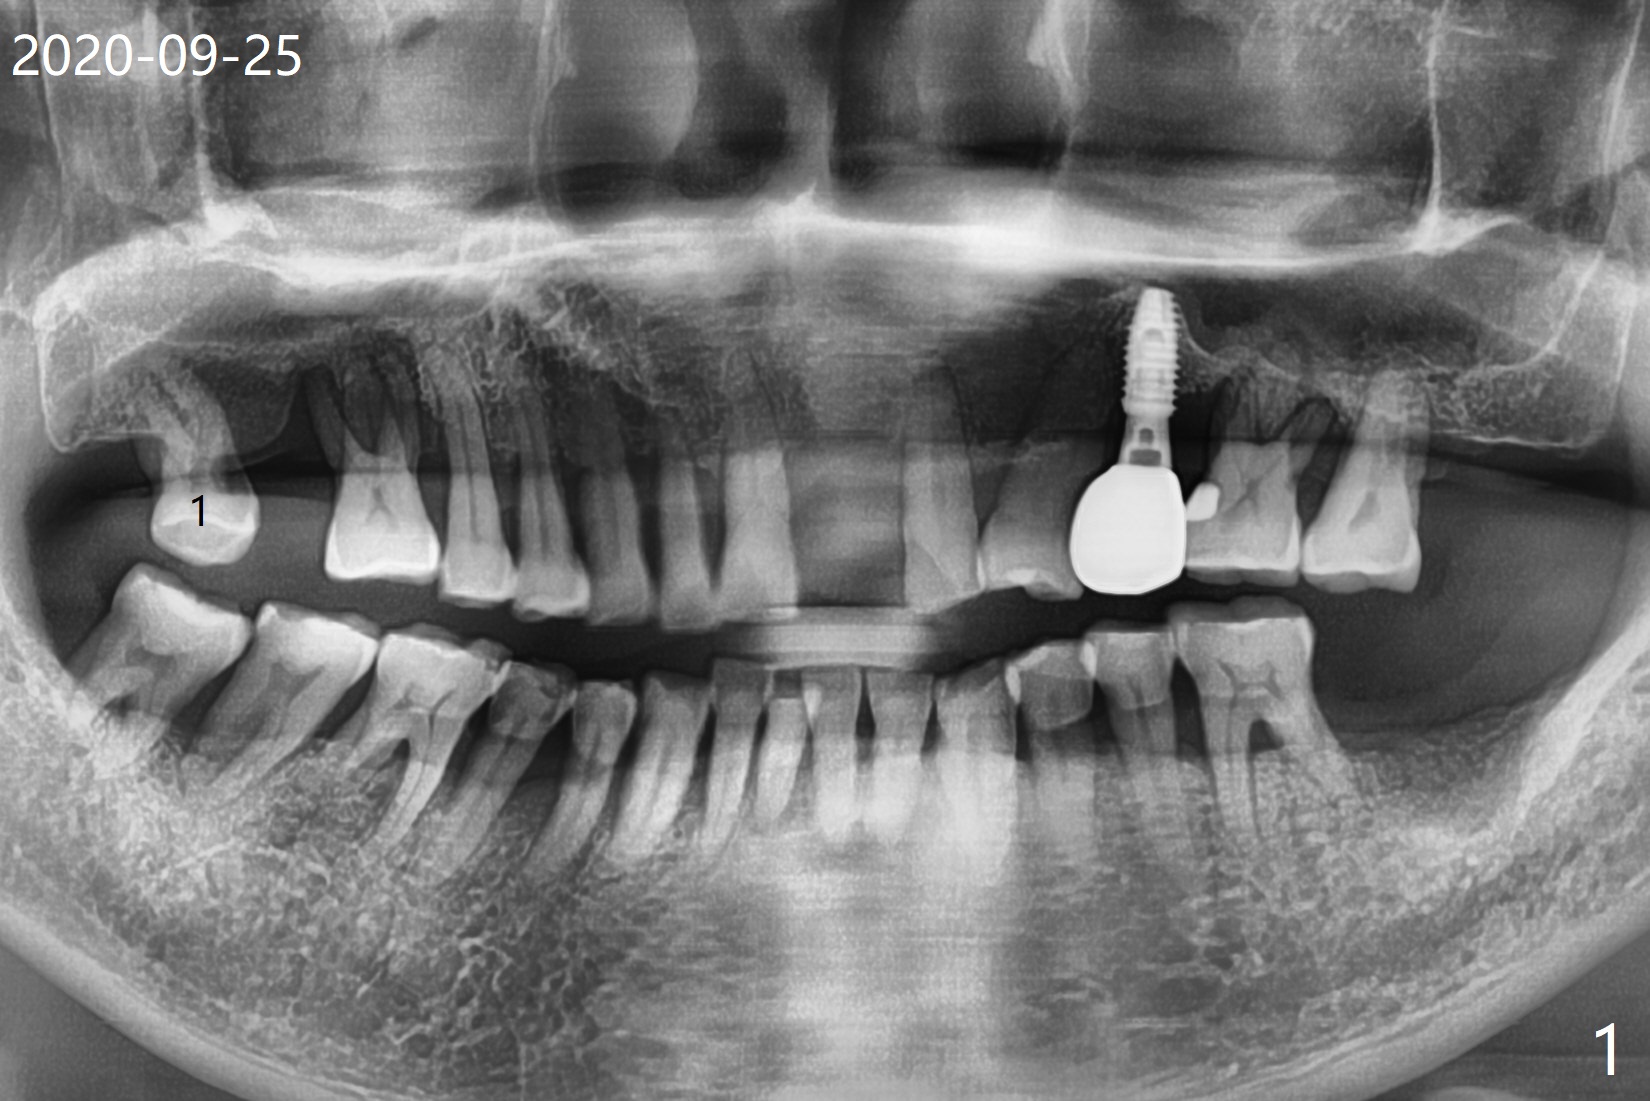

69岁,1号牙无症状(图一),去外州照顾孙子前,准备修补或者拔除,去龋后发现涉及牙髓(死髓),使用P3(图二)试图切断牙周膜,但是发觉不是很利索(图三),有什么窍门?